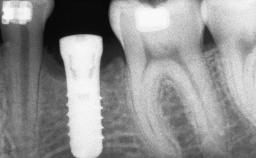

It is well known to clinicians that any removal of teeth will, over time, cause the dimensions of the alveolar ridge to be reduced by resorption of the bundle bone and by changes related to external modeling. This development is particularly evident in the crestal region with its thin buccal bone that consists of bundle bone almost entirely. The facial bone will rapidly resorb as blood supply from the periodontal ligament gets disrupted (Araújo and Lindhe 2005). There is no reason why traumatic tooth loss should not have the same consequences. It takes more than achieving implant osseointegration for a treatment outcome to be considered successful. No deficiency of bone or soft tissue is acceptable when an ideal esthetic outcome is the goal. Several articles (Sanz and coworkers 2011; Vignoletti and coworkers 2011) have reported on techniques of improving the alveolar ridge for implant treatment, notably focusing on protecting tissues from resorption.